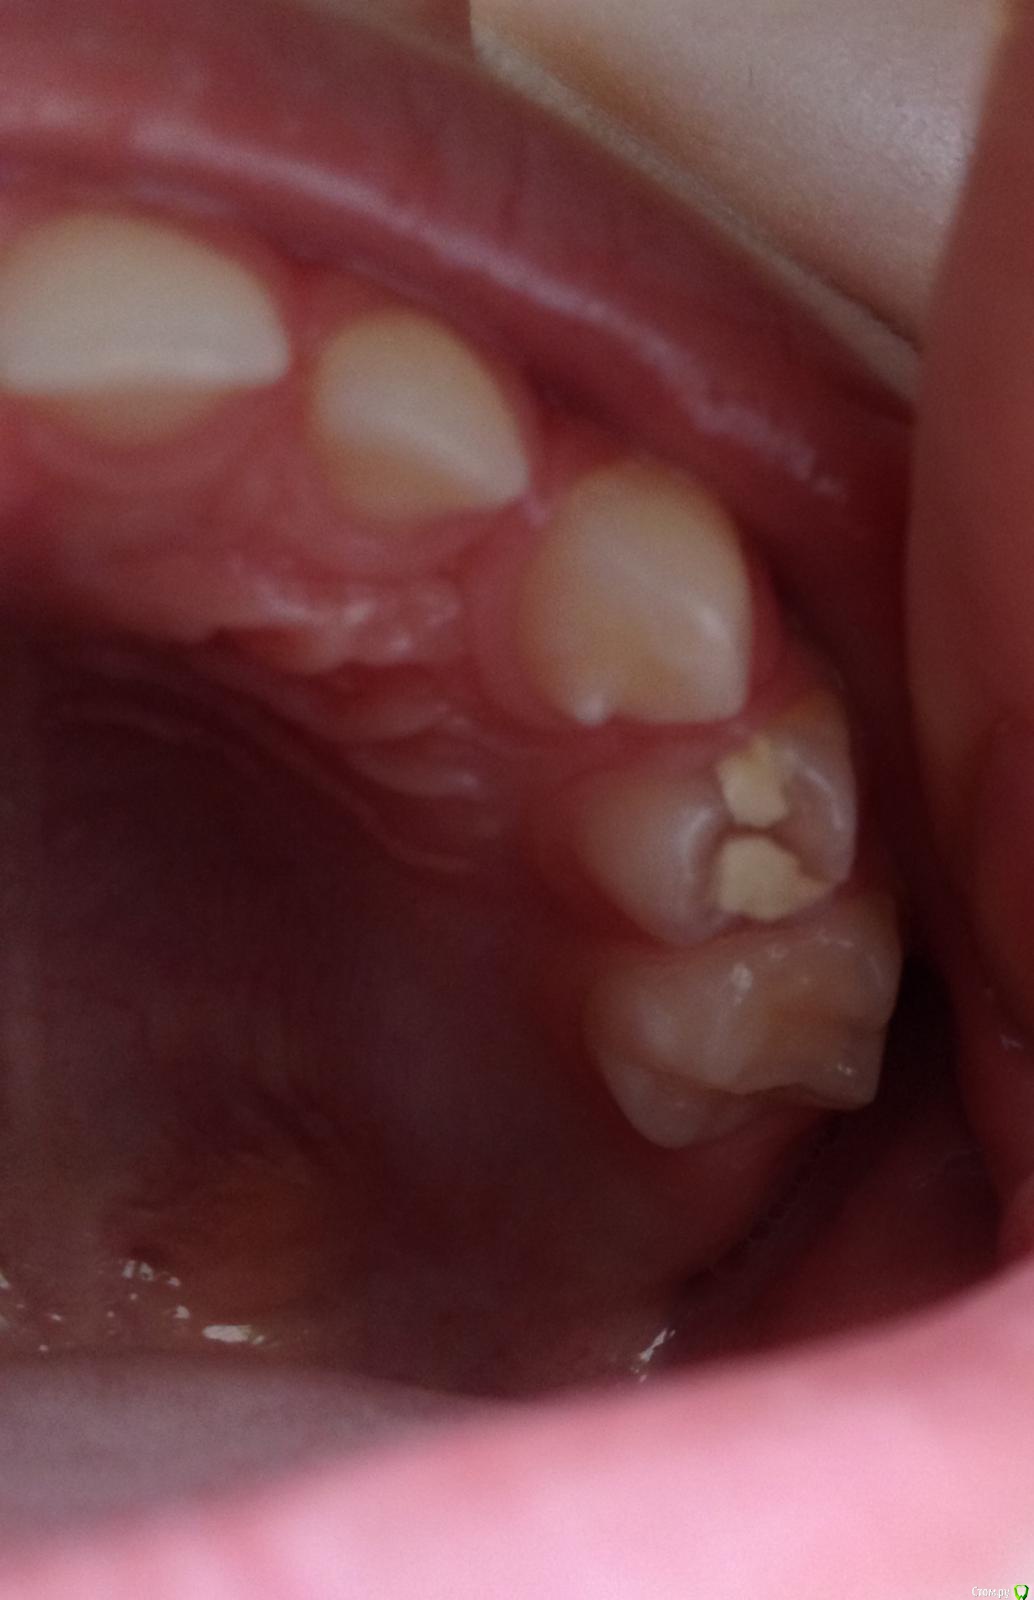

Аиdа Опубликовано 12 августа, 2016 Поделиться Опубликовано 12 августа, 2016 Здравствуйте!Нужно мнение независимых экспертов)У ребенка (4 года) кариес верхнего жевательного зубика ( 4-ка по-моему). Год назад лечили без бормашины, в частной клинике в Белграде, поставили какую-то супер пломбу. Вылетела через полгода примерно. Вчера наконец-то пошли в бесплатную детскую стоматологию уже в Москве. Зуб не беспокоил, просто надо же все-таки) В общем, действия врача - зеркало, потом замешал пломбу, потом вата вод щеку и пломбу на зуб. Все, свободны. Я не фанат бормашины, но надо же как то обрабатывать кариозную полость, это даже логично. Даже ничем не обработал нам дырочку, даже водой не брызнул, не говоря о какой-нить антисептичесокой обработке. Может там остатки пищи были, теперь под пломбой что там может начаться мне страшно. (зубы после еды конечно почистили, но все-таки)Я конечно не профессионал и многого могу не знать и не понимать в этом деле, но чувствую что что-то очевидно не так.Прошу посоветуйте что делать? P/S Забыла, что врач все-таки до пломбы подул воздухом на зубик. Не знаю как этот прибор называется, извините. Ссылка на комментарий

Аиdа Опубликовано 13 августа, 2016 Автор Поделиться Опубликовано 13 августа, 2016 Узнали. Ответ - полость правильной формы, нет смысла сверлить. Раньше была пломба. Ссылка на комментарий